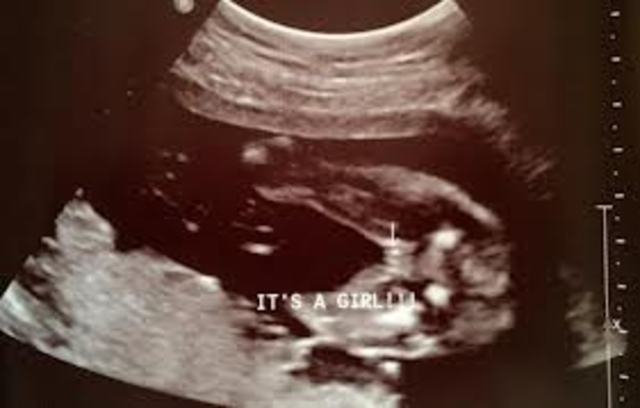

• Sex is Determined (week 16)

Sex is Determined (week 16)

The gender can be determined in a ultrasound.